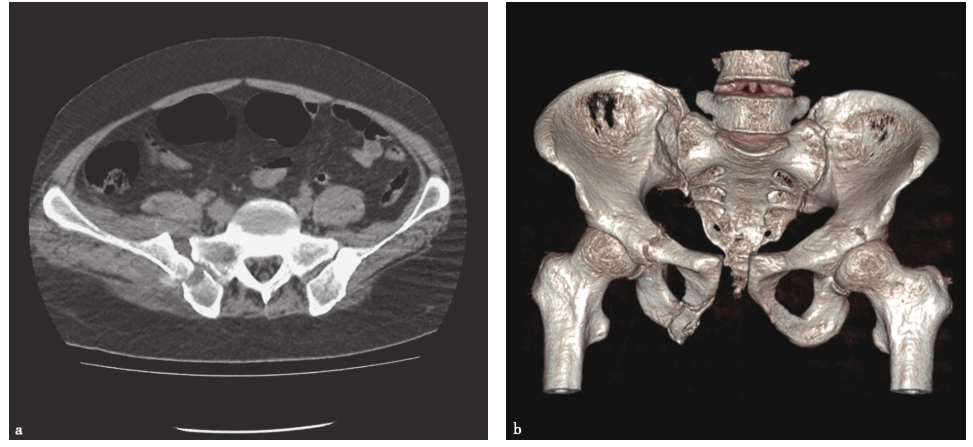

使用CT检查可以充分显示骨盆后方与韧带的结构。尤其是当骶骨骨折伴有大量肠气和粪便时,骨盆X线片容易造成漏诊,这时CT检查就非常有帮助。CT三维及多平面重建可获得任意平面的图像及任意旋转的三维立体图像,为临床医师整体、全面观察骨盆骨折提供了直观立体的图像,为骨折类型的诊断及手术设计提供了极大的帮助。骨盆受到外力损伤后骨性三维成像可清晰、完整地显示整个骨盆损伤后的形态变化及骨折情况,特别是对有移位的断端,在三维重建模式下可全面地了解断端上下、左右、前后的移位及程度,对于X线片不能发现疑似的隐匿性骨折,也可以在多平面重建成像中得以证实或排除。因此,三维成像的结果对实施手术的方式和骨折的固定有很重要的指导作用,并可依此对患者进行预后评估。对于确定骨盆背侧损伤的机制,CT检查时可以发现通过骶骨的损伤是压缩伤还是剪切力损伤。骶髂关节移位程度对于确定背侧损伤的稳定性是很有价值的。若关节张开的程度继续加大,后方韧带将断裂,损伤将变为不稳定型(C型)。CT还有助于了解有无髋臼骨折。很多接近前柱的耻骨支骨折容易合并髋臼骨折,近年来发展起来的三维CT对骨盆骨折的诊断帮助更大。Obaid报道了174例骨盆骨折病例,其中51%被X线片漏诊,最后由CT确诊,这些骨折大多发生在骶髂区域(图2-14)。

图2-14 骨盆骨折CT表现

a.CT显示双侧骶骨骨折;b.CT三维重建显示右骶髂关节间隙增宽,耻骨联合分离,右髋臼横行骨折。